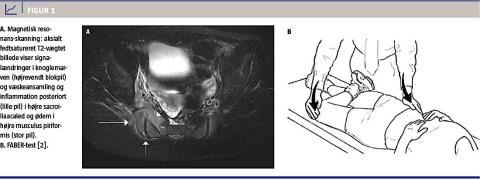

På mistanke om septisk sakroiliitis og begyndende tværsnitssyndrom blev patienten sat i behandling med ampicillin, dicloxacitin og metronidazol givet intravenøst, og overflyttet til et andet sygehus mhp. akut magnetisk resonans (MR)-skanning af columna totalis og det lille bækken. Skanningen viste unilateral sakroiliitis med knogleødem mest udtalt på højre side (Figur 1A). Behandlingen blev ud fra den positive bloddyrkning med vækst af gruppe B-streptokokker ændret til meropenem givet intravenøst og fusidin givet peroralt med efterjustering til cefuroxim givet intravenøst og fusidin givet peroralt. I alt blev der givet antibiotisk behandling i to uger intravenøst og fire uger peroralt. Patienten var fuldstændigt restitueret uden sequelae efter fem måneder.

historien. Prædisponerende faktorer for infektionen kan være tidligere traume, insektbid, svær atopisk dermatitis og akut furunkulose, men den kan også ses hos immunsuprimerede patienter og patienter med seglcelleanæmi. Patienten i sygehistorien havde ingen af disse prædisponerende faktorer. Specifik klinisk undersøgelse af sacroiliacaleddet foretages ved FABER-test (Figur 1B). Patienten lejres på ryggen, og herefter placeres patientens ene fod på det modsatte knæ. Hoften er nu flekteret, abduceret, udadroteret og ekstenderet. Undersøgerens ene hånd placeres på spina iliaca anterior superior og den anden på det flekterede knæ, herefter presses der nedad. Testen er positiv, når patienten mærker smerte posteriort [2].